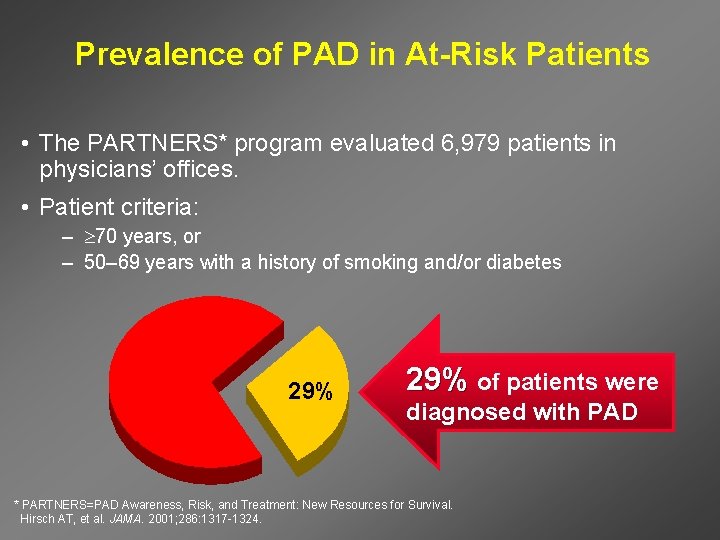

Prevalence of PAD in At-Risk Patients • The PARTNERS* program evaluated 6, 979 patients in physicians’ offices. • Patient criteria: – 70 years, or – 50– 69 years with a history of smoking and/or diabetes 29% of patients were diagnosed with PAD * PARTNERS=PAD Awareness, Risk, and Treatment: New Resources for Survival. Hirsch AT, et al. JAMA. 2001; 286: 1317 -1324.